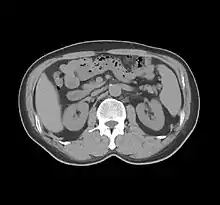

Sir Godfrey Newbold Hounsfield CBE FRS HonFREng[1] (/ˈhaʊnzfiːld/ HOWNZ-feeld; 28 August 1919 – 12 August 2004)[2][3][4][5][6] was a British electrical engineer who shared the 1979 Nobel Prize for Physiology or Medicine with Allan MacLeod Cormack for his part in developing the diagnostic technique of X-ray computed tomography (CT).[7][8][9][10][11]

His name is immortalised in the Hounsfield scale, a quantitative measure of radiodensity used in evaluating CT scans. The scale is defined in Hounsfield units (symbol HU), running from air at −1000 HU, through water at 0 HU, and up to dense cortical bone at +1000 HU[12][13] and more.

While on an outing in the country, Hounsfield came up with the idea that one could determine what was inside a box by taking X-ray readings at all angles around the object. He then set to work constructing a computer that could take input from X-rays at various angles to create an image of the object in "slices". Applying this idea to the medical field led him to propose what is now known as computed tomography. At the time, Hounsfield was not aware of the work that Cormack had done on the theoretical mathematics for such a device. Hounsfield built a prototype head scanner and tested it first on a preserved human brain, then on a fresh cow brain from a butcher’s shop, and later on himself. On 1 October 1971, CT scanning was introduced into medical practice with a successful scan on a cerebral cyst patient at Atkinson Morley Hospital in Wimbledon, London, United Kingdom.[16] In 1975, Hounsfield built a whole-body scanner. The principles of computed tomography developed by Hounsfield remain in use today (2022).